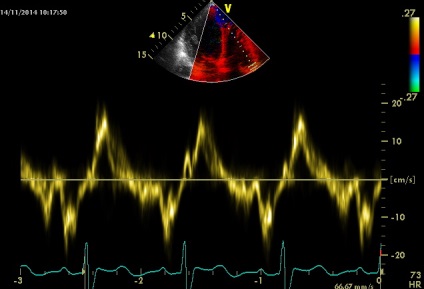

Sinus Valsalva - egy zseb-szerű szerkezet határolt szálas gyűrűt szelepcsappantyú, és az illető semiiunaris aorta fal, annak felső határa - sino-csöves csatlakozás. A falakat a két szinusz van a szája, a jobb és a bal koroanrnyh artériák, és hívják a jobb és a bal koszorúér sinus, és a maradék egyharmad - a nem koszorúér. A beteg egy diszkontinuitás az aneurizma a jobb coronaria sinus Valsalva (ünnepelte gyakrabban), mint látható parastrenalnyh szakaszok rövid és hosszú távú (egy lejtőn) tengelyeken. Számos egyéb, kevésbé gyakori aneurizma orrmelléküregek, még kevésbé egyidejűleg 2 vagy 3 (nem tévesztendő össze egy egyszerű kiterjesztése aortagyök szintjén az orrmelléküregek, ellentétben, amelyek továbbra is legyen tarsoly alakú kiemelkedés a fal, mint a mi beteg). A formáció egy ilyen aneurizma egy patológiás állapottal vegyületet struktúrák bázis szelep szórólapok és aorta fal. Fistulák (kóros anasztomózis) a szinuszok szintet, és anélkül, aneurizma (pl, amely különféle fertőző endocarditis). Csakúgy, mint az aneurizma nem bonyolítja egy hosszú szünet (és általában nem, hogy klinikailag). A rés a kialakulását a sipoly kiváltható trauma, szívbelhártya-gyulladás, magas vérnyomás, stb de néha spontán. A szünet alakul súlyos volumen túlterhelés, olyan funkciókkal, hemodinamikus megnyilvánulások, attól függően, hogy melyik kamrában visszaáll az aortából. Ebben az esetben, a reset határozzuk meg a jobb kamrai kiáramlási traktus (2. típusú), egy jelentős növekedést véráramlást a bal kamrai kiáramlási traktus (disztálisan a sipoly, miközben a szisztémás keringésbe csökken). Drámaian megnövekedett a nyomás a jobb kamra (amint azt a gradiens tricuspidalis regurgitáció + jelei megnövekedett nyomás a jobb pitvarban). De pulmonális sávval egy reflexszerűen hipovolémia, amíg részlegesen „védett” (görcs) az ilyen akut volumen túlterhelés (fokozott jelei rezisztencia lehet számítani). A helyzet sürgető, és előírja szívsebészet.

1. A Doppler spektrum májvéna szisztolés diasztolés fázis sokkal gyorsabb, bár a növekvő nyomás a jobb pitvarban kellett volna kevesebb. Ez nem korrelál sem közvetlen mutatók (flow TC öklendezés), vagy közvetett - nincs kollabirovaniya ARH az ihletet. (Még mindig túl félénk megkérdezni kapcsolatos technológia - gyakran látom, hogy bizonyítottan hosszú rekordot a máj vénás áramlási spektrum légúti változékonyság van a legtöbb ellenőrző térfogat indít, ha a beteg légzési mozgások, hogy csak néhány különálló cikluson lehet elérni.)

1. A Doppler spektrum májvéna szisztolés diasztolés fázis sokkal gyorsabb, bár a növekvő nyomás a jobb pitvarban kellett volna kevesebb. Ez nem korrelál sem közvetlen mutatók (flow TC öklendezés), vagy közvetett - nincs kollabirovaniya ARH az ihletet.

Mérje tünetek szerves hiánya várható változások a spektrum kifejezett tartós PV feltehetően a természet az akut túlterhelés és megemelkedne a diasztolés vérnyomás PP